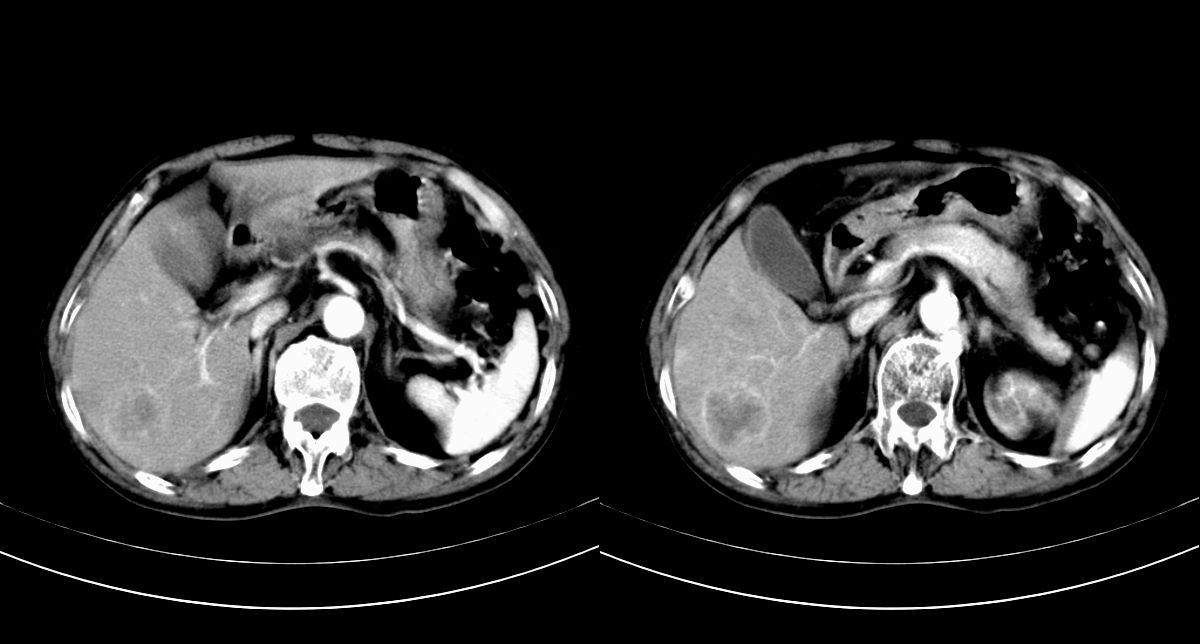

男,79y,无不适。体检发现肝脏占位。

肝内多发低密度结节,增强动脉期明显强化,门脉期逐渐下降,内有液化坏死区。

诊断:

肝细胞癌(结节型)

鉴别:肝转移癌。

支持多发结节巨块型肝癌,建议查afp。

巨块型肝癌伴肝内转移.

肝内转移瘤,查原发灶吧。

肝内多发低密度结节灶,增强动脉期明显不规则环状强化,;门脉期逐渐下降,肿瘤壁厚薄不一,内有坏死液化区。

诊断:典型的肝转移癌